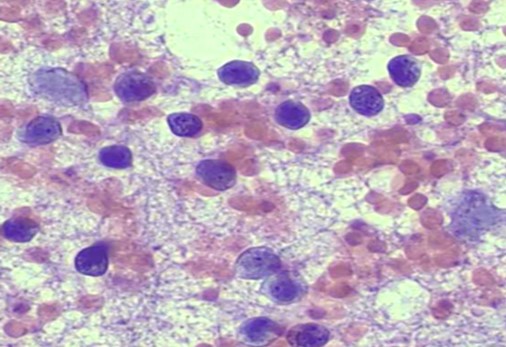

Investigations: Hb: 9.8, TLC (DC): 1.92 (56/37/0.5/6.1/0), ESR: 44 mm/hr, RF, Anti-CCP: <10,7, USG neck: Multiple enlarged LN (Ib, II-V) bilateral with loss of fatty hilum, FNAC: Histiocytes aggregates with scanty necrosis, Biopsy: Histiocytosis with scanty necrosis.

Diagnosis: Kikuchi disease